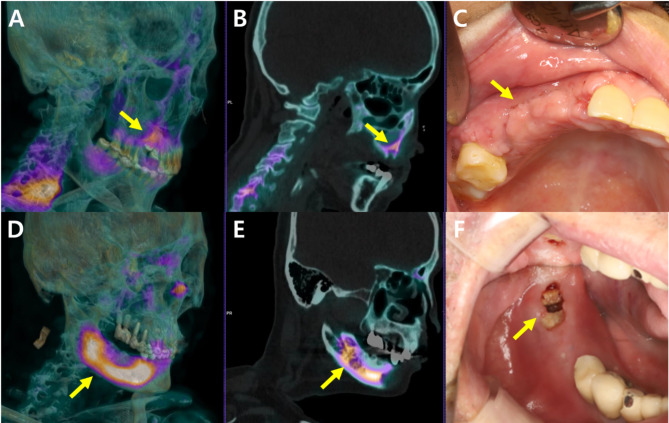

Background: Medication-related osteonecrosis of the jaw (MRONJ) is a challenging condition often associated with long-term use of anti-resorptive medications. Accurate diagnosis is essential, but predicting the prognosis is particularly difficult due to the high likelihood of recurrence after surgery. This study assesses the utility of quantitative values from bone SPECT/CT as predictors of surgical outcomes in MRONJ patients.

Materials and methods: We analyzed a cohort of 57 MRONJ patients who underwent surgical treatment. Preoperative bone SPECT/CT scans were used to obtain the maximal SUV (SUVmax) of MRONJ lesions and the ratio of the SUVmax to the mean SUV of a reference region (rSUVmax). Logistic regression analysis was performed to evaluate the relationship between preoperative SUVmax and rSUVmax and surgical outcomes, adjusting for confounders such as age, sex, diabetes, type of bone-modifying agent, MRONJ-affected sites, and stage.

Results: Both SUVmax and rSUVmax values increased with the progression from MRONJ stage 1 to stage 3 and were higher in the No Resolution group compared to the Complete Resolution group. Multivariate logistic regression analysis revealed that higher rSUVmax values were significantly associated with poor surgical outcomes (OR, 1.51; 95% CI, 1.07-2.14), whereas SUVmax values were not significantly associated (OR, 1.05; 95% CI, 0.98-1.13). Preoperative MRONJ stages did not significantly predict MRONJ resolution.

Conclusion: rSUVmax from bone SPECT/CT may serve as a valuable prognostic tool for assessing MRONJ severity and predicting surgical outcomes. Incorporating rSUVmax measurements into clinical practice could enhance decision-making and improve patient management.